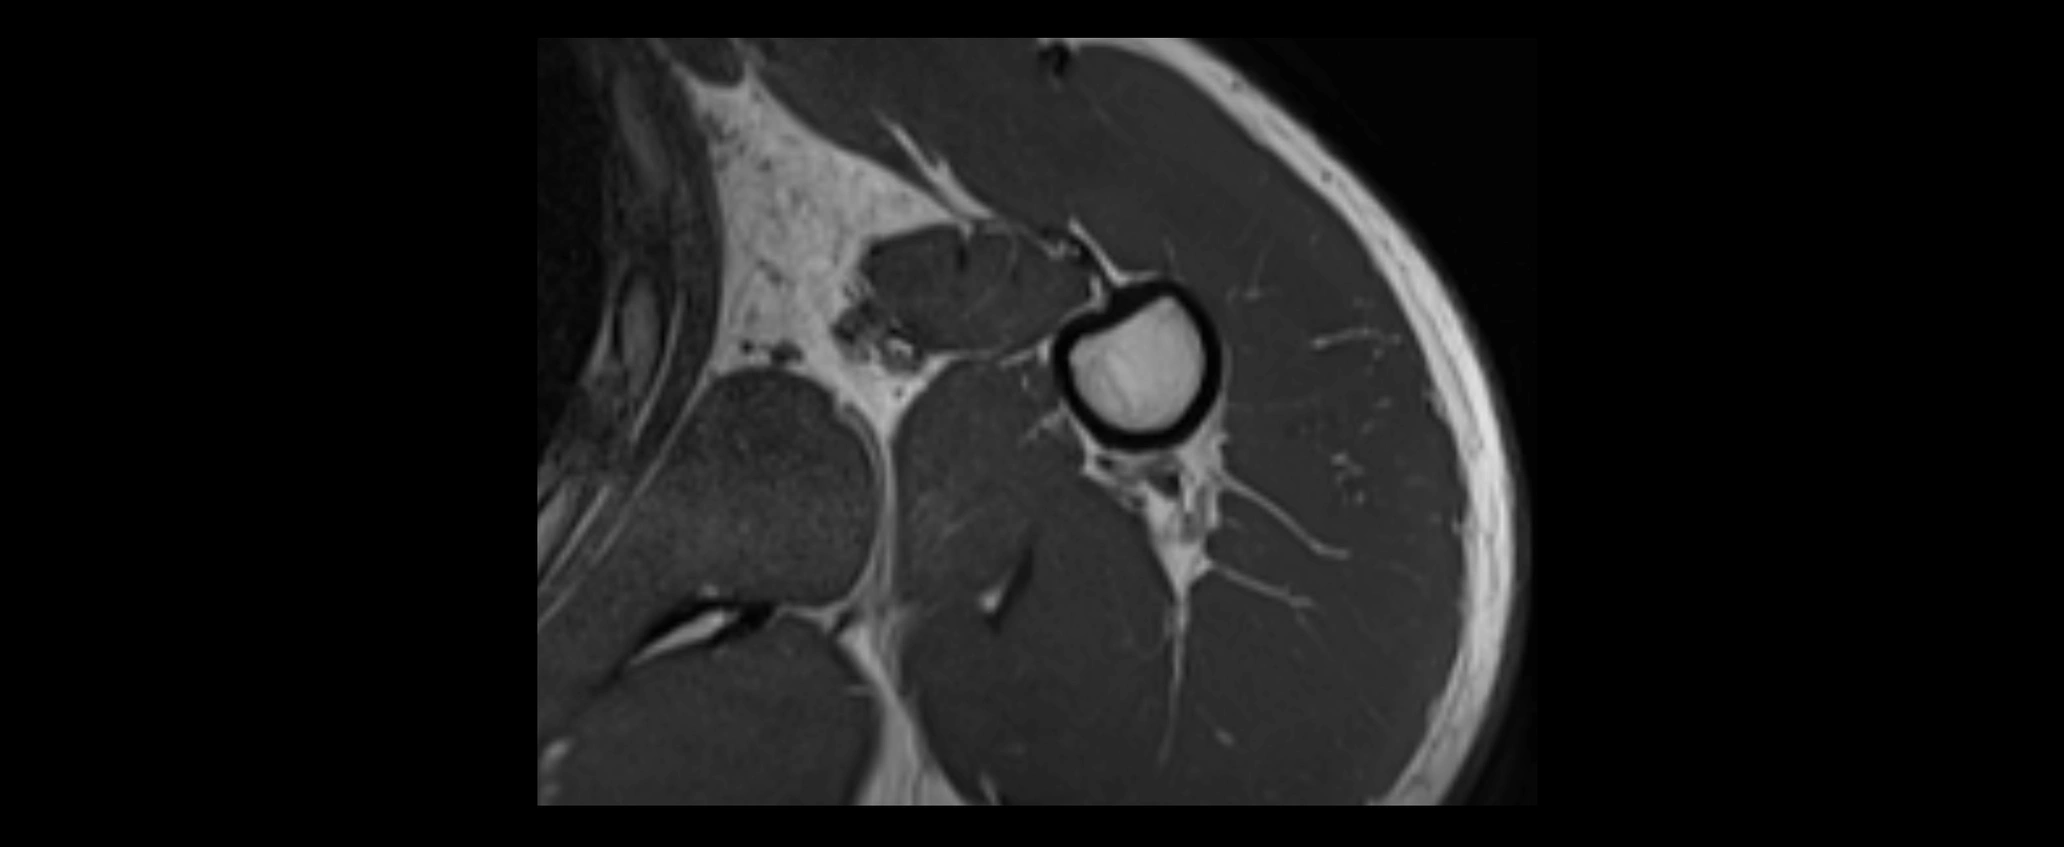

MRI images

image